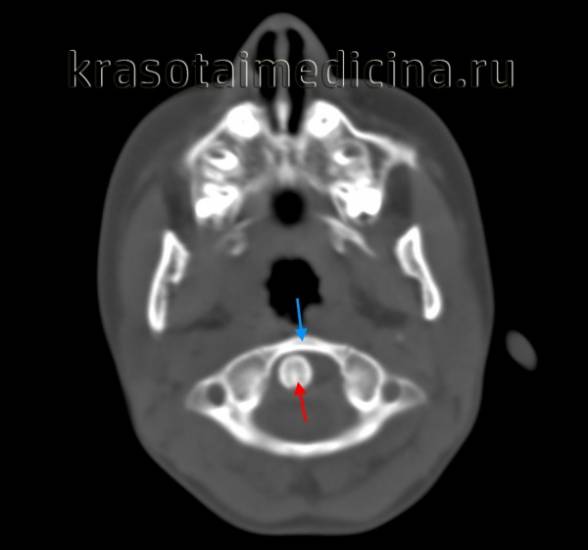

На КТ позвоночника можно увидеть уменьшение высоты диска и смещение суставных поверхностей. При подвывихе С1 наблюдается асимметрия между атлантом и зубом. МРТ позволяет уточнить состояние мягких тканей. Пациентам с подозрением на подвывих позвонков рекомендуется консультация невролога для выявления возможных неврологических нарушений. При хронических подвывихах и подозрении на ухудшение кровоснабжения головного мозга показана реоэнцефалография.